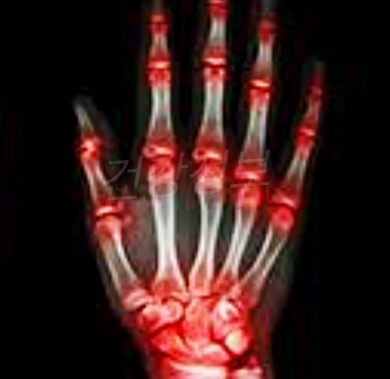

류마티스 관절염 초기증상

- 몸과 관절이 뻣뻣해 지는 증상

- 관절 부분의 발열과 붓는 증상(주로 손가락 마디나 손목)

- 근육량의 감소

류마티스 관절염 초기증상은 각 단계에 따라 나눠 질 수 있습니다.

제일 처음 관절 막의 염증으로 인한 관절의 붓기와 통증을 일으 킵니다. 면역 세포가 주 염증 영역으로 이동하고 확액 세포수가 증가합니다.

다음 단계에서 조직은 염증이 증가하고 넓어집니다. 관절 공간과 연골 공간에 영향을 끼치게 되며 서서히 관절 연골을 파괴하고 연골의 손실에 의해 관절이 좁아지기 시작합니다.

아직까지는 관절기형의 모습을 나타내진 않으나 다음단계까지 진행이 되면 심각한 단계입니다.

손상된 관절 연골의 상실 되어 연골 아래 뼈가 노출되어 있습니다. 환자들은 관절통, 부종, 움직임의 제한이 있고, 오전에 일어나면 경직된 느낌을 받으며 근육 위축등의 통증을 느끼게 됩니다.

가장 마지막 단계는 염증 과정이 감소하고 섬유 조직과 느슨한 뼈가 형성되고 관절이 작동하지 않습니다.